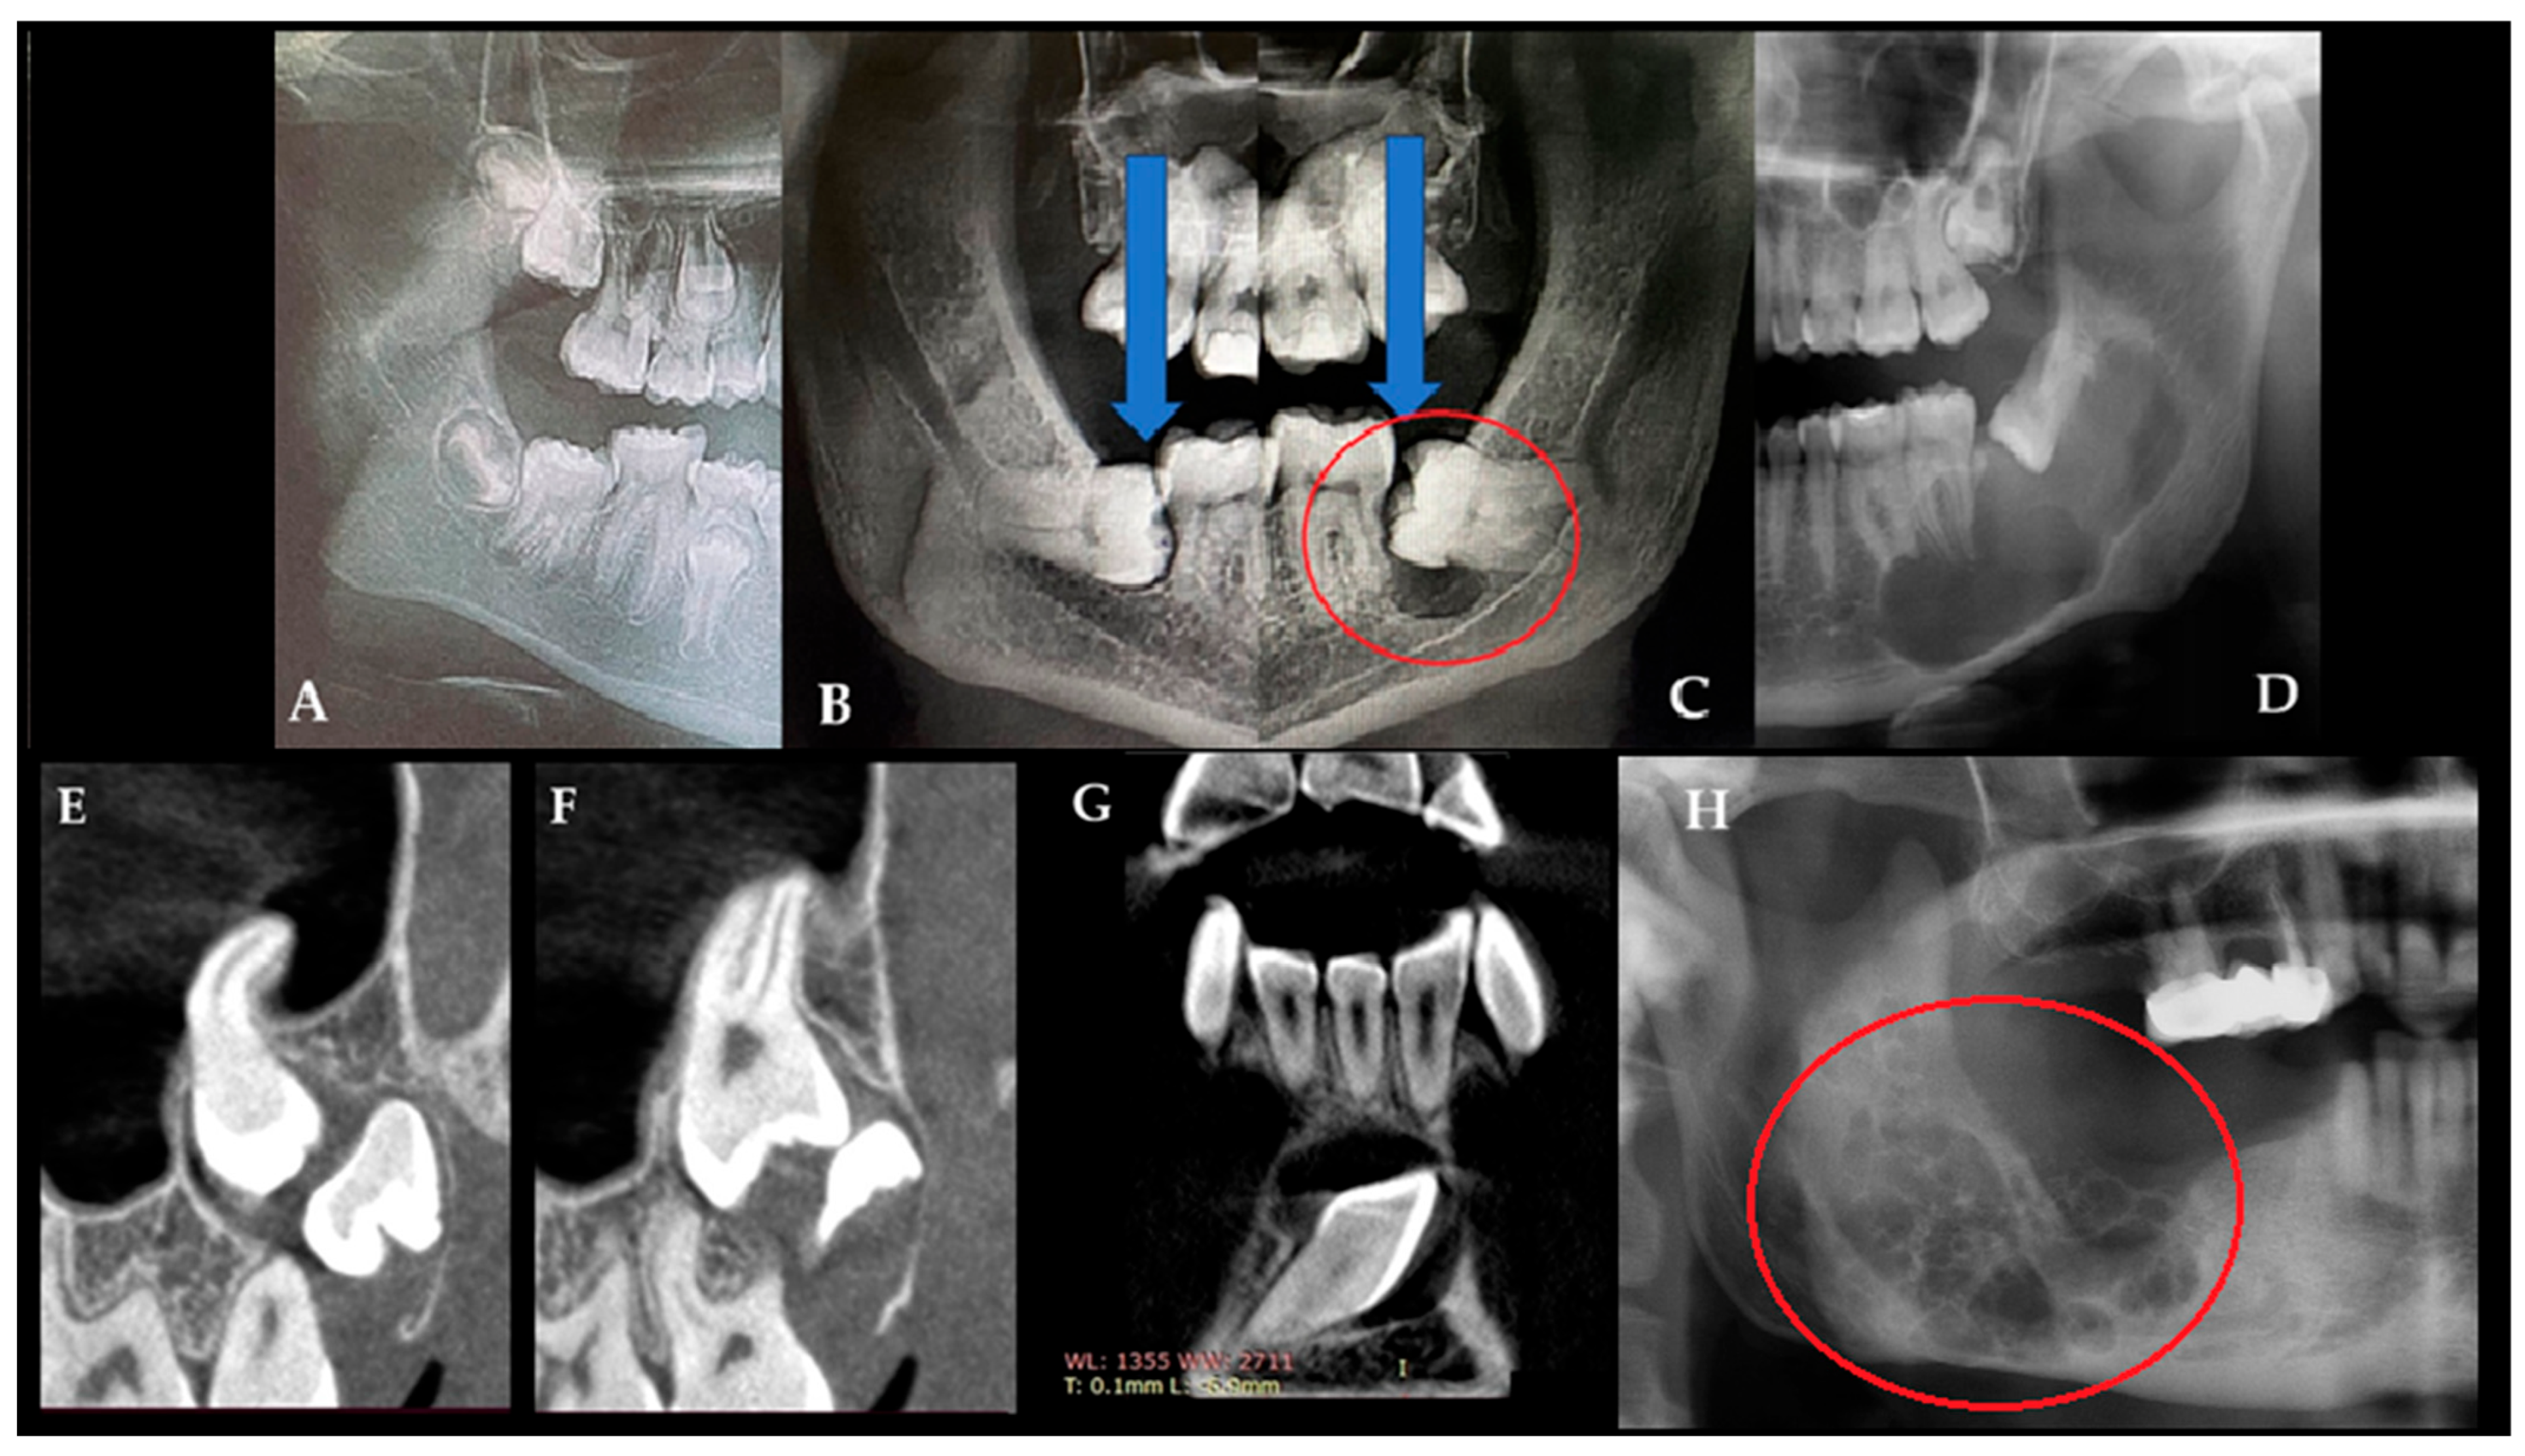

OPG is a useful initial screening tool for identifying bone cysts, lesions, and dental abnormalities. Quite often, a differentiation between dental follicles and typical cystic lesions of odontogenic and non-odontogenic origins can be assessed, as well as between solid lesions and other radiolucent, radiopaque, and mixed-appearance lesions [11,12]. Frequently, each cystic cavity in a juvenile patient should be differentiated between the following radiolucent cysts or cyst-like lesions: dentigerous cyst/follicular cyst (DC/FC), eruption cyst (EC), odontogenic keratocyst (OKC), unicystic ameloblastoma (UAM), radicular cyst, solitary bone cyst (SBC)/traumatic bone cyst, odontogenic myxoma (OM), or similar radiolucent unilocular lesions [9,10,11,12,13,14]. Routinely used OPG is quite a valuable diagnostic tool for finding any early-stage bone lesions, cysts, and tumors, and it can also be used for diagnostics with respect to teeth position, jawbone anomalies, and estimations of the dento-alveolar status of juvenile patients just before planned orthodontic treatment [15]. In cases of atypical bone architecture, such as a soap-bubble appearance, septated cystic lesions, calcifications, or irregular borders, cone-beam computed tomography (CBCT) is recommended to refine diagnoses and guide further diagnostic or surgical management. On the other hand, in juvenile patients, any enlargement or asymmetry in dental follicles surrounding retained or unerupted teeth might suggest the presence of a follicular cyst or indicate other tooth-related lesions. Sometimes, they can also cause odontogenic sinusitis when inflamed. It is worth identifying any asymmetry greater than 4 mm in any of the dental follicles and, if necessary, improving diagnostics with CBCT (Figure 1).

According to Bhardwaj et al., a dentigerous cyst (DC) is typically associated with the crown of an unerupted or partially erupted tooth and presents as a well-defined, asymptomatic, unilocular radiolucent lesion, which is sometimes accompanied by cortical expansion. Differential diagnosis should include radicular cyst, odontogenic keratocyst (OKC), ameloblastoma, ameloblastic fibroma, and odontoma [13,14]. CBCT provides a more detailed evaluation of jawbone lesions. In odontogenic tumors, particularly odontogenic myxoma (OM), characteristic CBCT features have been described, including internal septations forming triangular or rectangular spaces that create a “tennis-racket” or “honeycomb” appearance, scattered septa with or without tooth displacement or root resorption, and extension between dental roots with possible cortical breach and soft-tissue involvement [11,12,13,14]. During routine OPG screening, orthodontists can obtain valuable information not only about tooth position and jawbone relationships but also about the presence of potentially concerning bone lesions [15]. The role of CBCT is quite essential in evaluating the scope of bone changes, asymmetry, cortical perforation, resorption of dental apices, and the scope of bone invasion, as well as investigating the surrounding vital structures in detail, like the inferior alveolar nerve, maxillary sinus, and the proximity of dental buds [10,11,12,13,14,15].

A generally healthy 13-year-old boy was referred for a routine orthodontic consultation. Medical history revealed no relevant conditions, including prior trauma, infection, or surgical treatment. At the start of orthodontic treatment, routine OPG screening demonstrated normal bone structure, mixed dentition, and appropriate jaw symmetry and alignment. Initial treatment included removable braces and oral hygiene (Figure 2: R—right side; L—left side). Routine OPG is a commonly used screening radiograph. In this case, it was performed as part of an orthodontic assessment to evaluate the presence and position of permanent teeth, the stage of dentition, and the presence of remaining deciduous teeth prior to further treatment. The bone structure of the jawbones is irrelevant in Figure 2. Initial orthodontic screening revealed no radiological signs of cysts and tumors. The shape and size of dental follicles surrounding both mandibular second permanent molars were normal. Bone structure was sustained, teeth buds were well positioned and symmetrical, and no worrisome radiological signs were present. The patient had no significant bone swelling, cortical expansion, or any significant changes in the intraoral examination.

Control OPG radiograph after 18 months revealed the formation of a cystic lesion of radiolucent and unilocular appearance in the left retromolar area of the mandible (blue arrow). On the other hand, the right retromolar area was free of any disease, with normal bone contour and shape (red arrow). Because a left retromolar lesion was associated with a freshly, not fully yet erupted left mandibular second molar, an assumption of a follicular cyst (FC) was made. Since the lesion was unilocular and radiolucent, without any calcified or mineralized structures inside, a comparison with a cyst was made. In this case, the OPG showed no septations, ridges, or calcifications within the unilocular lesion (Figure 3). As the lesion progressed over time in the absence of clear clinical symptoms, CBCT imaging was performed to improve diagnostic assessment. If any suspicious findings, such as bone erosion, extracortical spread, resorption of adjacent teeth/roots, cortical bone erosion or swelling with a periosteal reaction, loss of bone structure with irregular borders, or other worrisome symptoms, are found on CBCT, a decision to perform either a biopsy or excisional biopsy should be made. The choice of approach depends on the lesion’s shape, size, and anatomical location within the jaw. The patient exhibited no worrisome swelling intraorally; their teeth were stable without any mobility, and bone asymmetry was not noted. In the following case, a needle biopsy did not reveal any fluid accumulation typical of a classic cyst of odontogenic origins.

Figure 1. Many radiolucent lesions with well-defined borders represent cysts within the oral cavity. Each developing tooth is surrounded by a small, round radiolucent area known as the dental follicle, which is typically well defined and less than 4 mm in diameter (A). During growth, maturation, and tooth eruption, the dental follicle can remain, reduce its shape, disappear in time (blue arrows indicate the dental follicle on the left side that progressively regressed and disappeared), or form a follicular cyst (red circle). This situation occurs mostly when it is associated with totally or partially unerupted teeth (B,C). Panoramic radiography (OPG) is a useful initial screening tool and can identify various cystic and cyst-like jaw lesions of different sizes, shapes, and locations ((D)—unicystic ameloblastoma, UA). In general, retained teeth and associated cystic cavities should be further evaluated using CBCT (EG). For comparison, a representative OPG of an odontogenic myxoma is shown in (H), demonstrating typical multilocular, lobulated (the red circle highlights the soap-bubble appearance) radiolucency with internal septations, a classic pattern that helps differentiate myxoma from simple cystic lesions. On the other hand, not all found cyst-like appearances on a routine OPG are a cyst; in these cases, CBCT is recommended to ensure that the dental follicle and formation of follicular cysts or any other cyst-like lesion do not have any worrisome symptoms, such as the following: bone erosion, teeth resorption, cortical swelling, any presence of bone irregularities, septa, or a mixed radiolucent–radiopaque appearance that might suggest the formation of a possible odontogenic tumor (abbreviation from image (G): I—inferior (lower border of mandible); WL/T (mm)—location of the follicle in CBCT in millimeters).